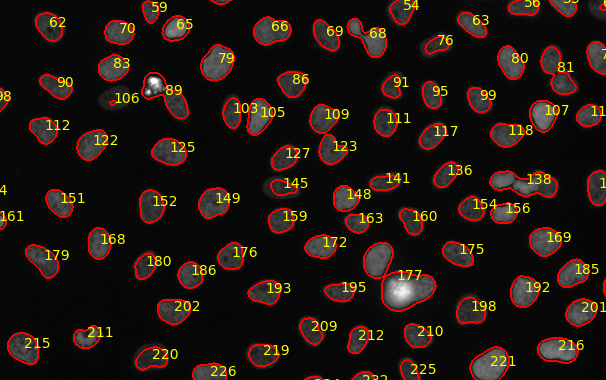

Galaxy Image Analysis: Capturing Mitoflashes

Workflow: https://usegalaxy.eu/u/bmcv/w/capturing-mitoflashes

Paper: https://doi.org/10.1097/j.pain.0000000000002642